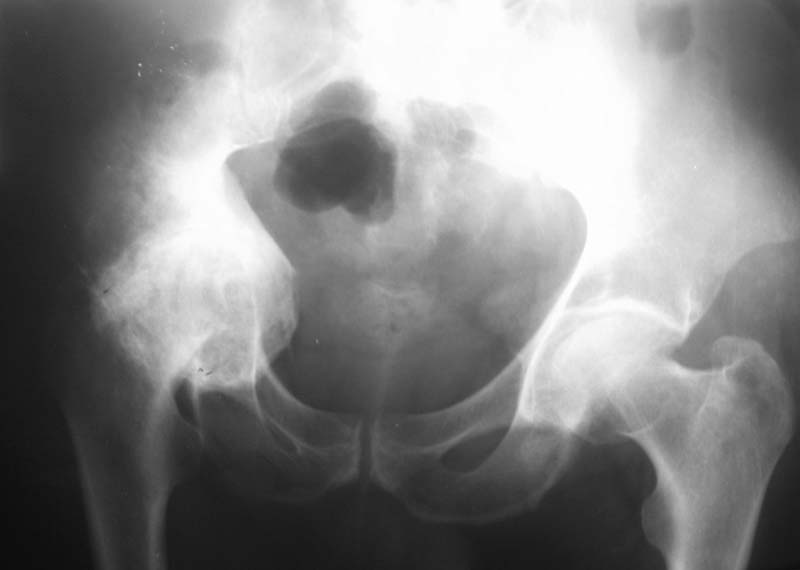

Мужчина, 54 г. В 12 лет перенес травму правого тазоберенного сустава.

Клинически движений в суставе нет, хотя при ходьбе беспокоят боли.

Предполагаем имплантацию <чашки> протеза в сформированное ложе без удаления головки бедра.

Ваше решение абсолютно адекватное и возражений нет, но проблема будет не в этом. У Вас будут сложности в 1) правильной ориентации чашки относительно истинной вертлужной впадины и 2) создании необходимого

"оффсета", попросту говоря, будет крайне сложно "оторвать" бедро от таза. Для этого мы в своей практике пользуемся расширенным передним и задним релизом, как правило, на это уходит достаточно много времени.

Безусловно будут большие технические проблемы с отделением бедра от таза. Ложе для чашки (кстати, какого типа?)придется формировать с нуля. Восстановить длину конечности - тоже проблема, учитывая атрофию окружающих мыщц. Кстати, каково укорочение конечности? В общем, можно получить весь букет технических трудностей протезирования и при этом не получить ни одного его преимущества... Мне кажется, это случай для артродеза.